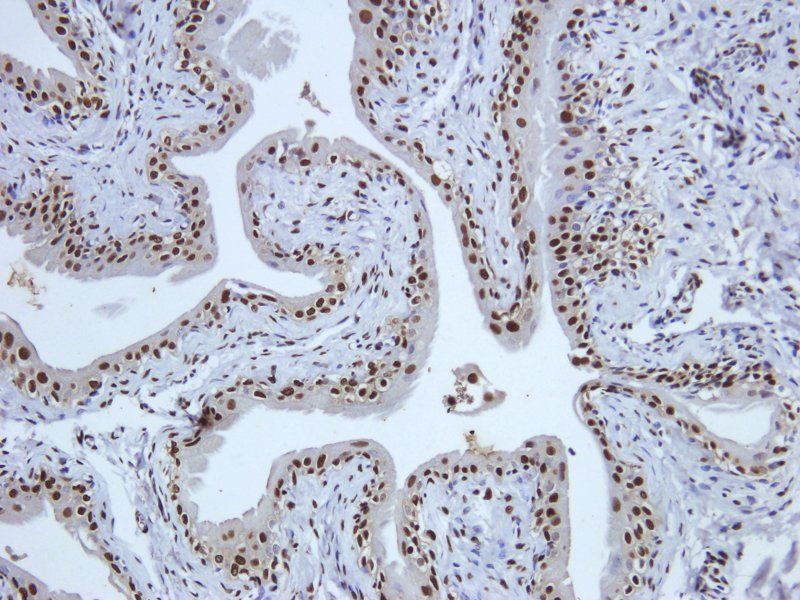

ELISA, IHC-P

应用稀释比例:IHC-P: 1:200